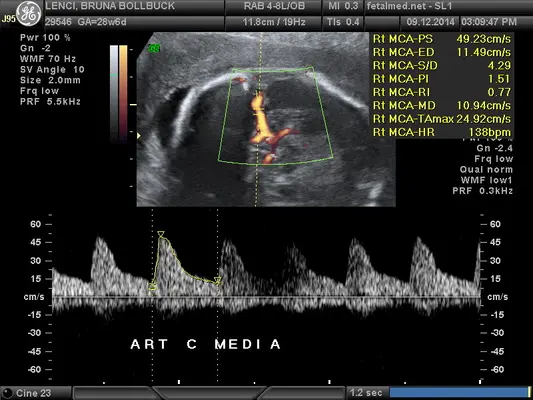

Velocidade de Pico Sistólico da Artéria Cerebral Média

Valores de referência da velocidade de pico sistólico da artéria cerebral média fetal para diagnóstico de anemia e…